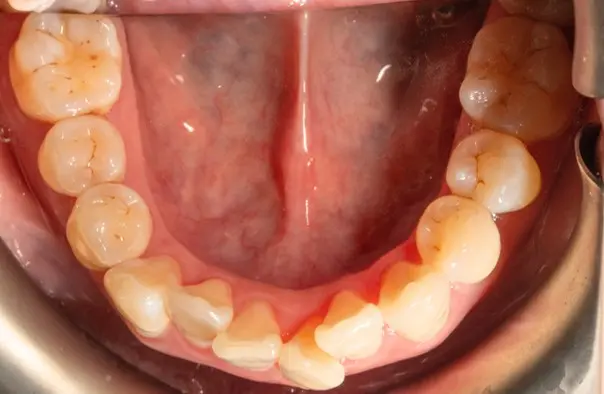

Crowding

Before